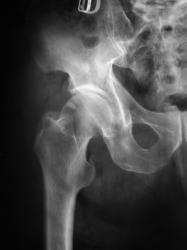

Косой перелом правой тазовой кости без смещения отломков. С момента травмы прошло около 1,5-2,0 месяцев. Пациент направлен "на контрольное исследование".

В верхнем наружном секторе головки бедренной кости визуализируется участок уплотнения вытянутой треугольной формы. Участок помечен желтыми стрелками. Рядом дифференцируется участок просветления - помечен красной стрелкой.

Может эндостальное омозоление перелома шейки бедра?

Валентин Львовим! По моему мнению имеет место кистовидная перестройка костной ткани, как проявление артроза тазобедренного сустава 3-й стадии. Стояние отломков удовлетворительное. Умеренно выраженная эндооссальная костная мозоль.

А почему бы не эностоз? (bone island)

Эностоз? Я за! Но он какой-то секторально-треуголный, мож какая-то функциональная перестройка структуры, в любои случае (ИМХО) это случайная находка.